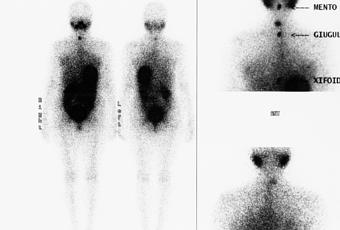

Hablamos de gammagrafía refiriéndonos a un examen que pertenece a la medicina nuclear. En esta prueba se puede detectar algún tipo de anomalías que pueden tener los huesos o en diferentes órganos del cuerpo.

El especialista inyecta un marcador, o lo que es lo mismo, un material radioactivo pero en pequeña cantidad. De esta forma es posible comprobar a través de imágenes si hay alguna infección en la zona que se quiere explorar, bien sean los riñones, pulmones, huesos… El material radioactivo se inyecta a través de una vena y éste, va recorriendo poco a poco el cuerpo. Con la ayuda de la gammacámara se detecta la cantidad del material radioactivo que se ha quedado en los órganos.

Gammagrafía ósea: Los valores que marca permiten detectar si hay algún tipo de infección como artritis, necrosis aséptica, tumor… fracturas y antigüedad de las mismas, trastornos óseos, enfermedad de Paget…